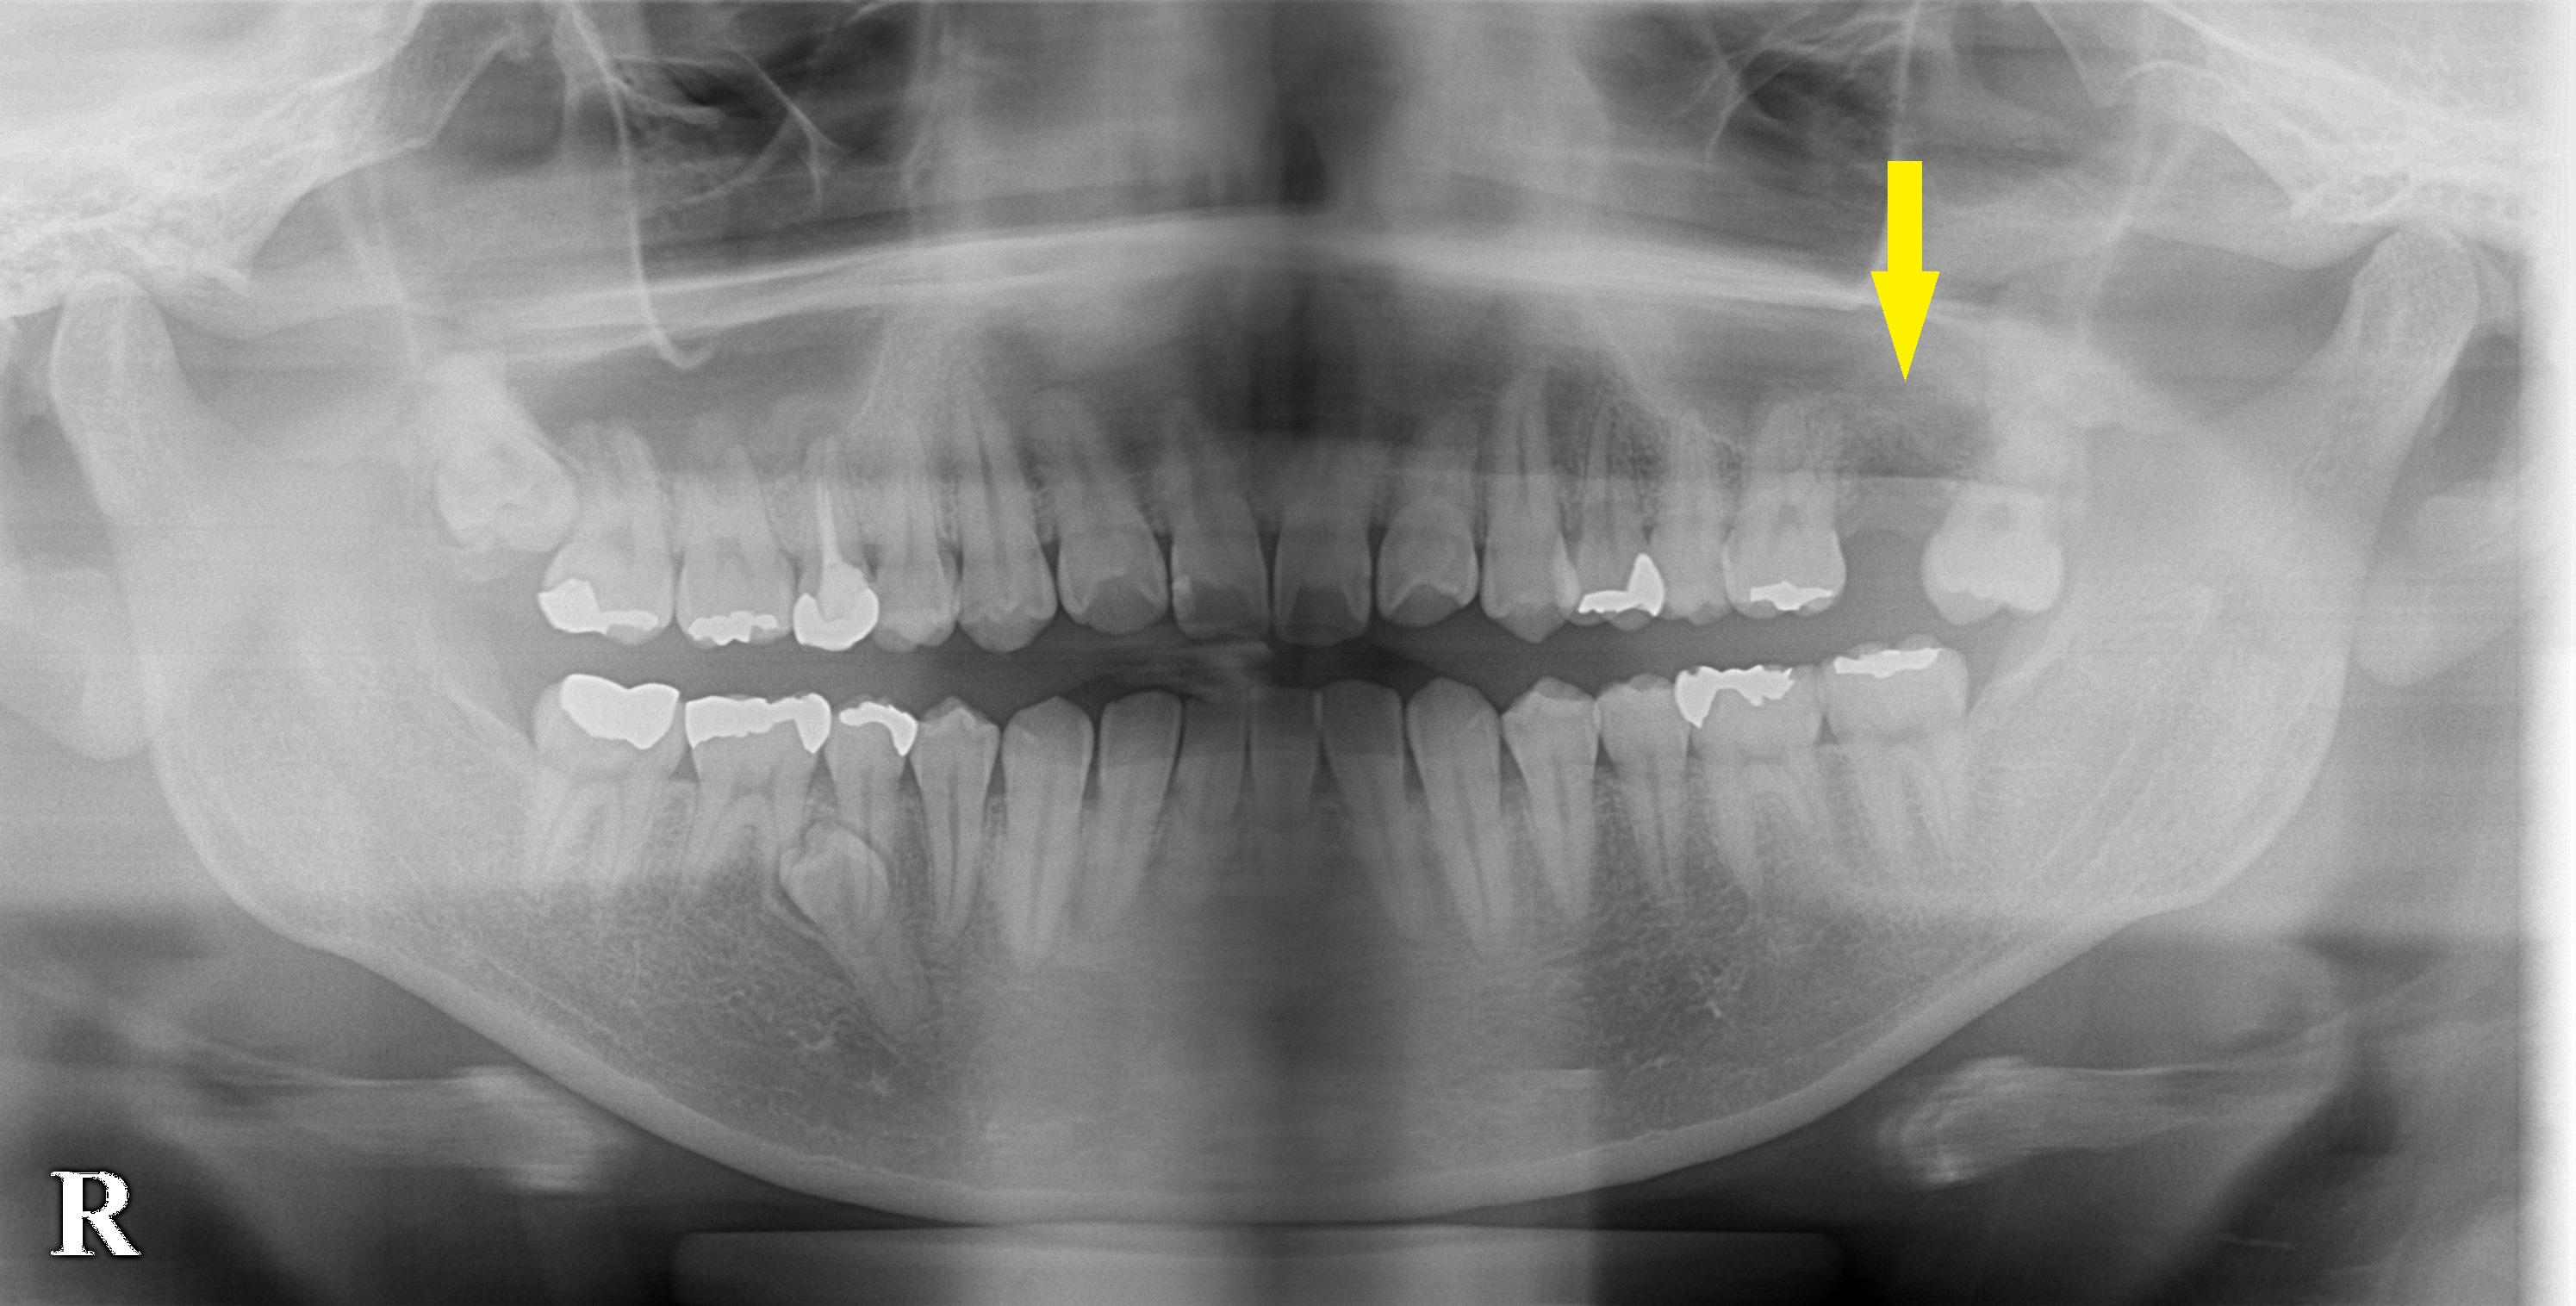

患者様は名古屋在住の30代女性。

左上顎の題二大臼歯を抜歯されて、インプラントかブリッジという治療方法がある説明されたそうですが、インプラントは骨が薄くて難しいと言われたそうです。

ブリッジの場合、後ろの親知らずと手前の第一大臼歯を削らなければならず、何とかインプラントができないものかと当院に相談に来られました。

CT撮影してみると、骨の厚さは、5mm程でした(下2段目の左右の写真)。

長さ10mm以上のインプラントを埋入しようとすると、ずいぶん骨が不足します。

そこで、ソケットリフトという、骨を増やす方法を併用すれば、インプラント治療が可能になると説明させていただきました。

その方法で同意を得られましたので、本日、ソケットリフトを行い、インプラント埋入術を施行しました。

下3段目の左右の写真で、

インプラントの上方にドーム状に骨が造成され、埋入がうまくいっている様子が、確認できます。